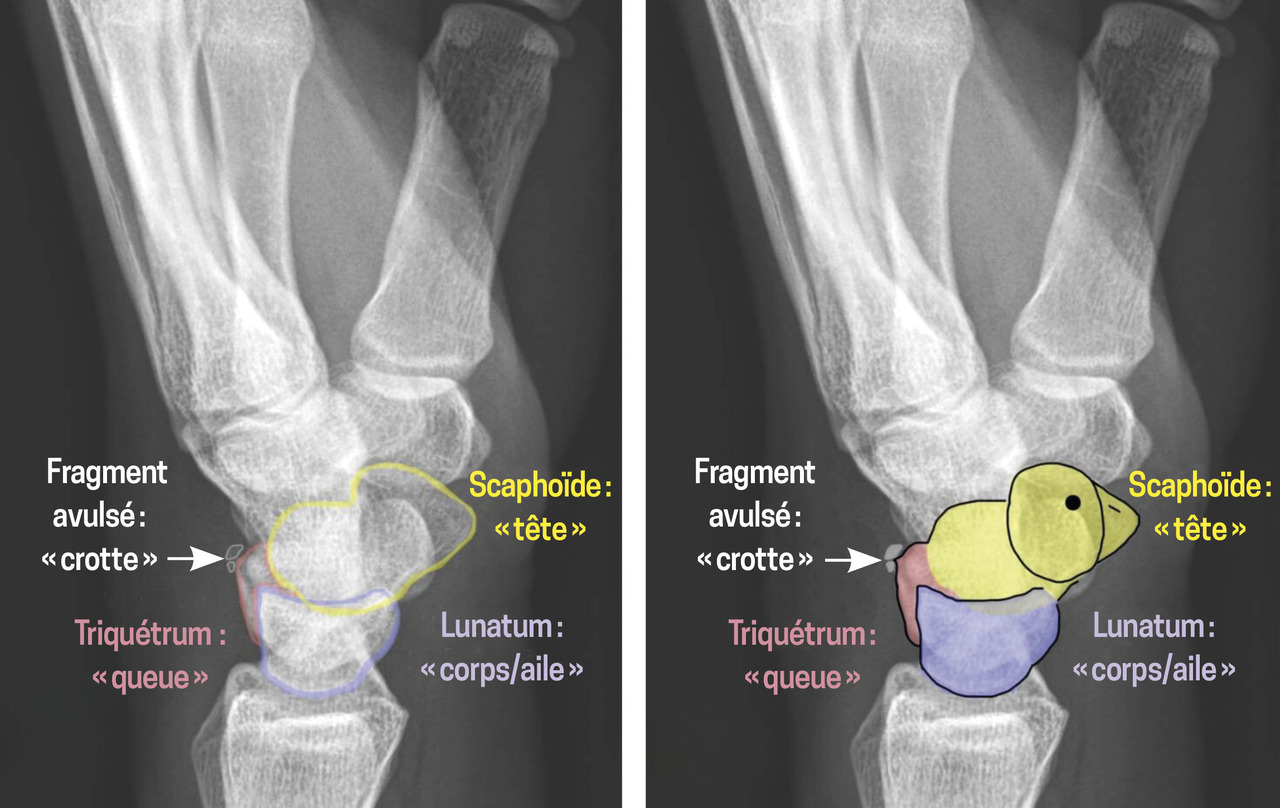

Les fractures du triquétrum sont les deuxièmes fractures carpiennes les plus fréquentes après celles du scaphoïde.1 Elles résultent d’un mécanisme d’impaction ou d’avulsion au niveau des sites d’insertion des ligaments intercarpiens (le triquétro-hamato-capital et le luno-triquétral), ainsi que du ligament radio-triquétral dorsal (fig. 1). Bien que généralement bénignes, ces fractures peuvent entraîner des séquelles fonctionnelles si elles ne sont pas identifiées et traitées. Or, la radiographie de face met rarement en évidence des signes clairs de fracture. En revanche, le « signe du canard qui fait caca » (pooping duck sign) est un repère radiographique spécifique de fracture dorsale du triquétrum en vue latérale : le fragment avulsé représente la « crotte », tandis que le scaphoïde, le lunatum et le triquétrum dessinent respectivement la tête, le corps et la queue du « canard »2 (fig. 2).